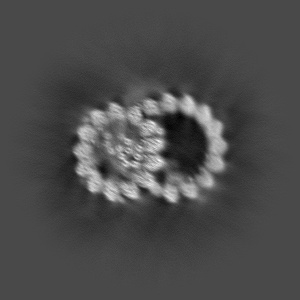

Local map of the mouse sperm doublet microtubule (Upper06)

Sample Organism: Mus musculus

Sample: Mouse sperm DMT

Structures of sperm flagellar doublet microtubules expand the genetic spectrum of male infertility.

Zhou L , Liu H, Liu S, Yang X, Dong Y, Pan Y, Xiao Z, Zheng B, Sun Y, Huang P, Zhang X, Hu J, Sun R, Feng S, Zhu Y, Liu M, Gui M , Wu J

(2023) Cell , 186 , 2897 - 2910.e19